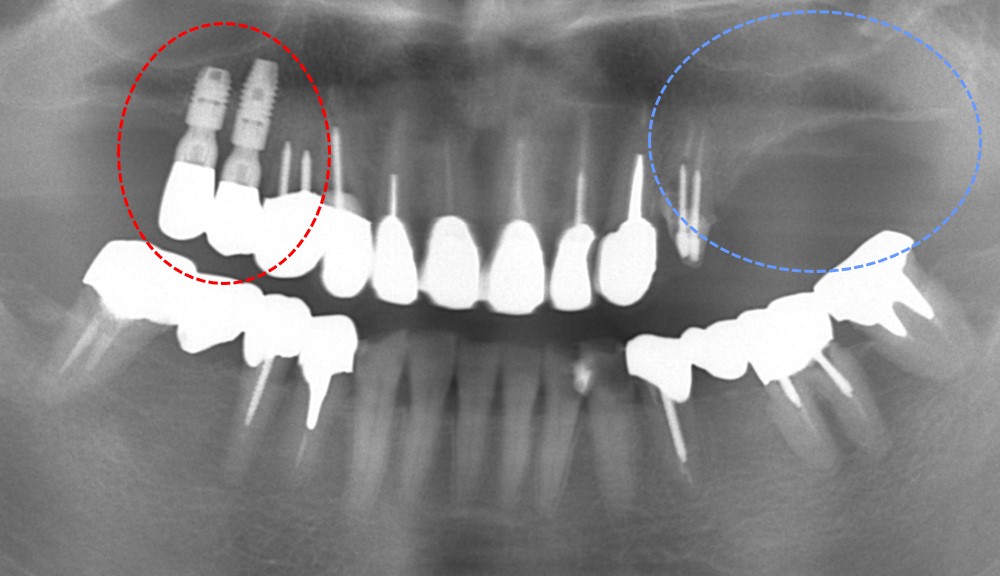

赤○部分は以前埋入したインプラントです。今回、青○部分の欠損部にインプラントを計画しています。

上顎には上顎洞という空洞があるため、黄色矢印の範囲内(骨がある部分)にインプラントを埋入する必要があります。骨を造成する方法もありますが、今回はこの範囲で2本のインプラントを埋入する予定としました。1本は10,72mmの骨幅に、もう1本は6.94mmの骨幅に埋入しなければならないため、9mmと6mmのインプラントを使用することにしました。

インプラント埋入直後の写真です。限られた骨幅にインプラントを埋入できています。

術後4年経過のレントゲン写真です。

インプラント周囲の骨も安定しており、良好に経過しています。

4年経過していますが今のところ良好に経過しています。予後が良好なことが最も重要なことと考えています。